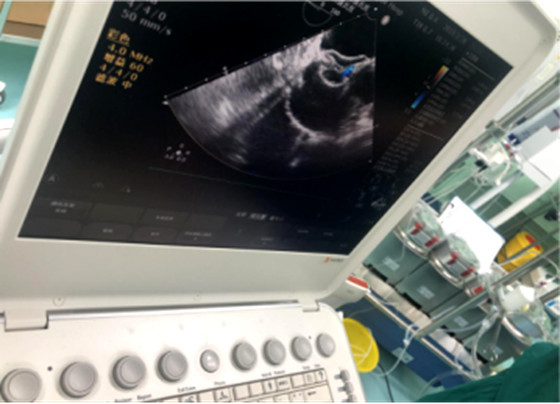

陈女士随即来到湘雅常德医院心胸外科就诊,心脏彩超提示为先天性心脏病:心脏超声检查提示陈阿姨的房间隔缺损范围较大、距上腔静脉的边缘较近。

近日,陈女士接受了湘雅常德医院首例超声引导下经皮房间隔缺损封堵术以及首例超声引导下经胸小切口室间隔缺损封堵术。

在黄日茂教授、龙隆教授的带领下,以及麻醉科的支持配合下,经过约30分钟的努力,心胸外科团队在陈阿姨的心脏中植入了22mmASD封堵器,术中超声显示封堵器位置、形态良好,房间隔分流消失,听诊杂音消失,手术顺利结束,参加手术的医生护士和陈阿姨的家人一样露出了欣慰的笑容。